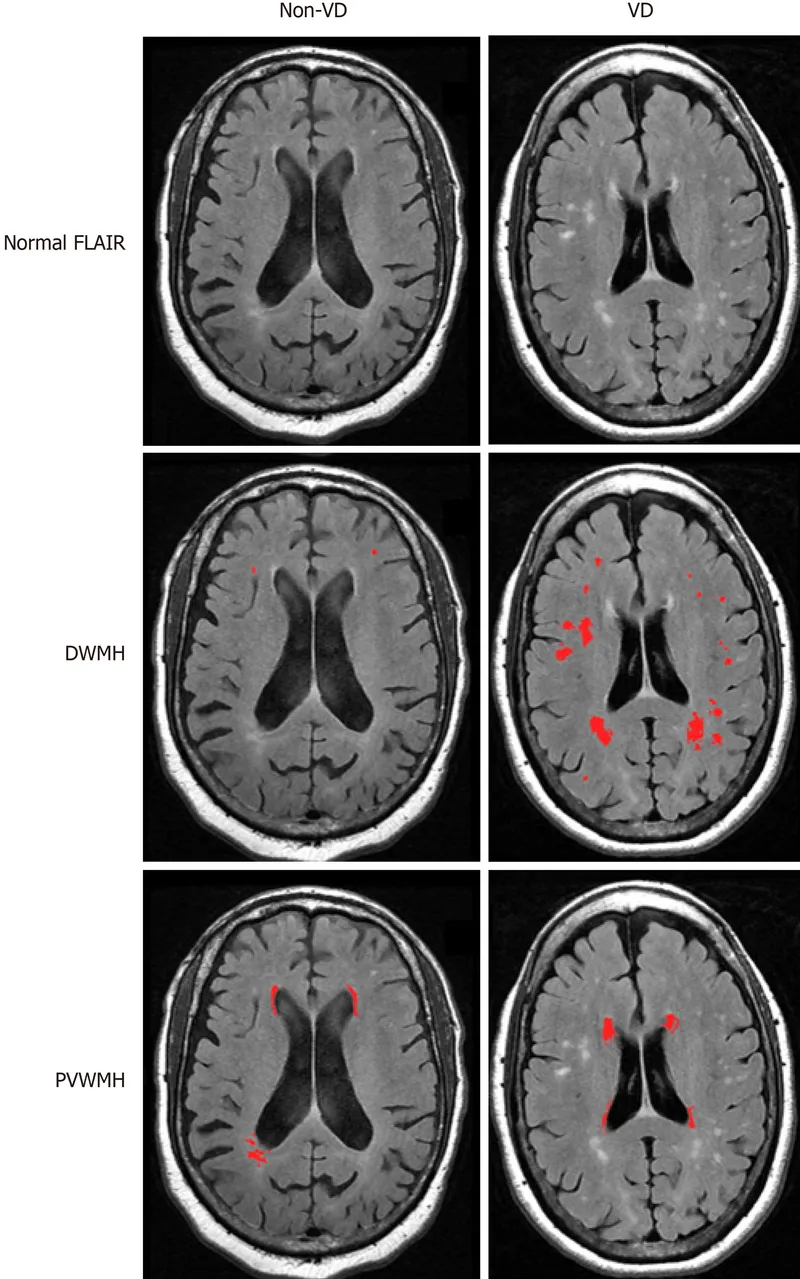

⭐ Vascular Depression Hypothesis: Late-life depression, especially with significant apathy and executive dysfunction, is often linked to underlying cerebrovascular disease. MRI may show white matter hyperintensities.

⭐ Late-onset depression (>60 y/o) has a stronger association with underlying cerebrovascular disease ("vascular depression") than early-onset depression.